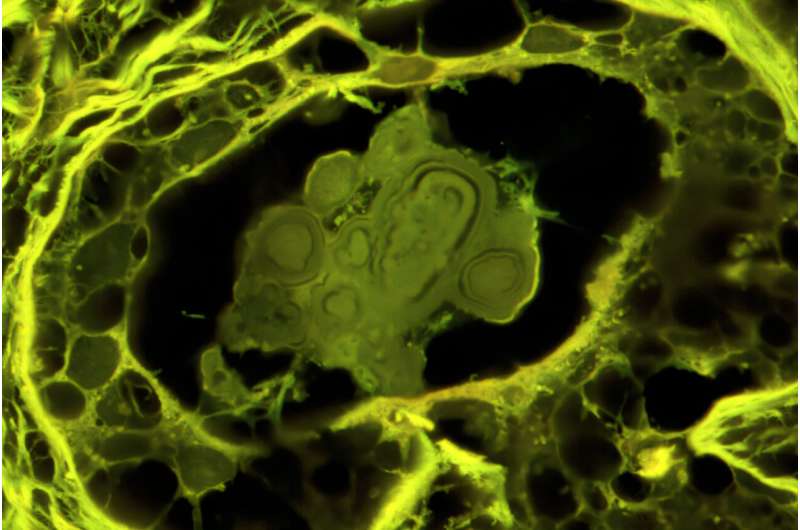

La nouvelle étude a examiné les échantillons de tissus biopsiés de maladies mammaires bénignes et de carcinome canalaire in situ qui avait été retiré lorsque les patientes ont subi une intervention chirurgicale dans le cadre d’une étude à long terme de la clinique Mayo. Pour documenter les caractéristiques minérales du BBD et du DCIS, les chercheurs ont utilisé 12 méthodes différentes pour caractériser les échantillons, y compris une suite de microscopes légers, laser et électroniques et techniques de rayons X et de spectroscopie Raman.

Les chercheurs ont constaté que les calcifications étaient faites de phosphate de calcium amorphe, un minéral avec la capacité de Shapeshift et de réorganiser, bien qu’il ait longtemps été supposé être le type de phosphate de calcium cristallin trouvé dans l’os, l’hydroxyapatite. L’équipe a analysé les couches des dépôts ACP pour tracer comment ils ont commencé comme de petites sphérules qui se sont fusionnées en nodules. Les nodules ont ensuite enterré les cellules et incorporé d’autres molécules, telles que les protéines, les substances cireuses et le cholestérol.

La forme et la progression de la calcification différaient dans les échantillons de BBD et de DCIS. Par exemple, le BBD avait plus de nodules sphériques avec une superposition concentrique, tandis que les calcifications cancéreuses avaient tendance à être plus allongées et irrégulières. Certains nodules cancéreux ont également montré une progression similaire à la caractéristique de fossilisation du bois pétrifié, a déclaré Fouke.

« Les types de nodules ACP que nous avons vus étaient complètement inconnus et établissent un tout nouveau schéma de classification entre BBD et DCIS », a déclaré Fouke. « Chacun a une genèse et une histoire de formation différentes, reflétant les changements dans la physiologie du sein qui à leur tour sont fortement corrélés avec le fait qu’un échantillon de biopsie a été désigné bénin, peut-être bénin ou suspect. »